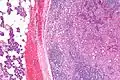

Micrograph of an acinic cell carcinoma (right of image) and acinar glands (parotid gland - left of image). H&E stain.

Basophilic, bland cells similar to acinar cells. Growth pattern: solid - acinar cells, microcytic - small cystic spaces mucinous or eosinophilic, papillary-cystic - large cystic lined by epithelium, follicular - similar to thyroid tissue.

These tumors, which resemble serous acinar cells, vary in their behavior from locally aggressive to blatantly malignant.